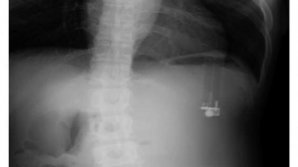

Тэги: желудок Гастроэнтеролог предупредил об осторожности в употреблении чеснока Ученые обнаружили "бактериальный допинг" чемпионов Наушник Apple AirPods продолжил работать внутри желудка В желудке кита, выброшенного на берег на Филиппинах, нашли 40 кг пластика Девочка шесть лет ела волосы и вырастила колтун в желудке Три члена семьи удалили желудки из страха перед раком "Надувная" таблетка позволит наблюдать за организмом пациента изнутри целый месяц Из 11-летнего ребенка московские врачи "выудили" 23 магнитных шарика Исследование показало, что насытиться запахом еды и похудеть вполне реально Ученые нашли еще один мозг в теле человека В Испании в желудке кита нашли 29 кг пластика Содержимое желудка свиньи оценили в полмиллиона долларов Учёные из Самары создали "вечный" йогурт Врачи обнаружили зажигалку в желудке у 49-летнего американца В Индии из желудка пациента извлекли 600 гвоздей Рыбаки достали из рыбы-гиганта 32 черепахи: видео Египетский врач достал из желудка пациента 39 гвоздей и зажигалку В аэропорту Киева поймали курьера с кило кокаина в желудке Ученые рассказали, через что лежит путь к сердцу женщин 1 ABCDEFGHIJKLMNOPQRSTUVWXYZ IMPORTANTE ALTELE